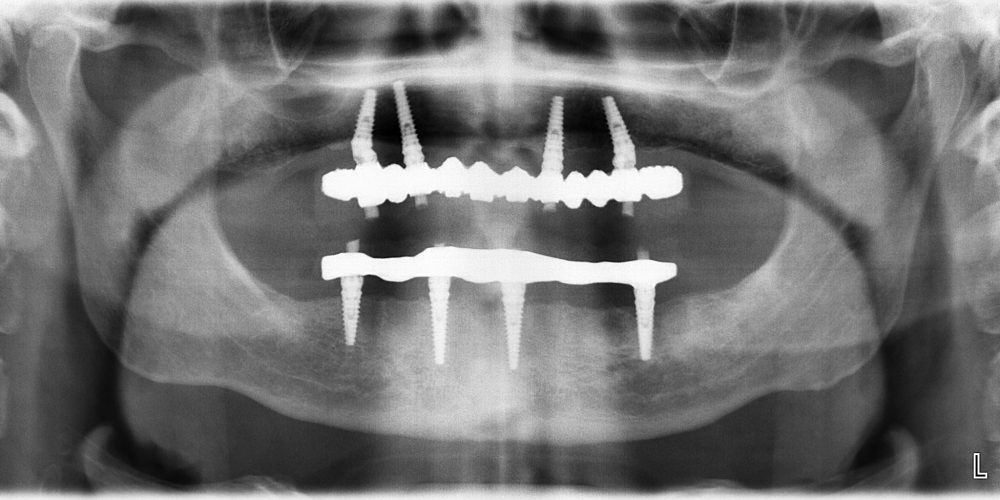

L’impianto dentale è una vite in lega di titanio che sostituisce la radice naturale del dente mancante. Agli impianti inseriti nelle ossa mascellari è applicato un perno moncone (detto abutment) che sostiene la corona avvitata o cementata. In questo modo viene ricreato totalmente il dente, dalla struttura interna alla corona esterna.

PROTESI COMPLETA SU IMPIANTI

In molti casi il paziente tollera con difficoltà la classica dentiera che appoggia esclusivamente sulle gengive soprattutto per la difficoltà di ottenere una buona stabilità della protesi. In alcuni casi si può ottenere la risoluzione del problema andando ad inserire 4 impianti sui quali verrà avvitata una protesi fissa (protesi All On Four) che potrà essere confezionata ed adattata nelle 24 ore successive all’intervento di implantologia. Grazie all’utilizzo delle diagnosi con TAC Cone Beam e al confezionamento di dime chirurgiche l’intervento risulterà molto rapido e dal dolore post operatorio molto contenuto.